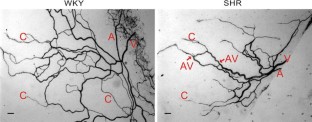

Structural microvascular rarefaction, defined by a loss of vessels, is a common characteristic of hypertension and has been associated with elevated microvascular resistance. However, determining the causal relationship between microvascular network structure and resistance requires a consideration of all pattern changes throughout a network. The objectives of this study were to determine whether microvascular rarefaction is associated with other network pattern alterations and to evaluate whether pattern alterations in hypertension necessarily contribute to increased microvascular resistance. Mesenteric tissues from age-matched (15–16 weeks) male spontaneously hypertensive rats (SHR) and normotensive Wistar-Kyoto (WKY) rats were harvested and immunolabeled for PECAM. SHR networks displayed a decreased microvascular area, arteriolar-venular (AV) length, number of AV branches, and number of capillary segments. In addition, SHR networks displayed increased AV connections per network compared to WKY networks. Based on network geometries, resistance per network was calculated using a computational model. For simulations with equal vessel diameter and with relative diameters based on reported intravital measurements, SHR microvascular network resistance was not elevated compared to the WKY level. Our results suggest that microvascular pattern alterations associated with hypertension are more complex than vessel loss, and that these combined alterations do not necessarily lead to elevated resistance.

Fig. 1